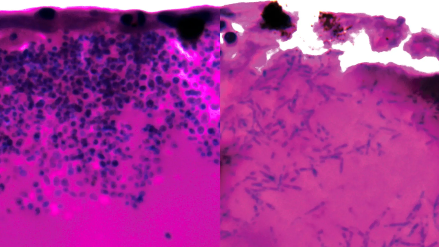

Ces observations ont révélé que le champignon développe des structures filamenteuses, probablement utilisées pour explorer son environnement et accéder aux nutriments indispensables à sa survie. Surtout, l’étude a mis en évidence une activation intense de gènes impliqués dans l’absorption et le transport du fer, un élément essentiel à sa croissance et à sa virulence. Cette dépendance au fer apparaît désormais comme un véritable talon d’Achille : priver Candida auris de cet apport ou perturber les mécanismes qui lui permettent de le capter pourrait freiner, voire stopper, le processus infectieux.